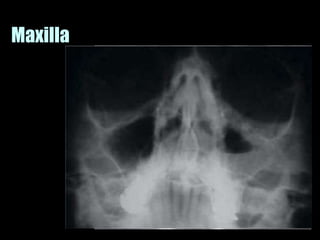

This document provides an overview of normal musculoskeletal imaging. It discusses basic x-ray concepts and densities. It then reviews normal anatomy as seen on x-rays of the skull, spine, pelvis, chest, and extremities. Key anatomical structures are labeled on example x-rays for the shoulder, hip, knee, and foot. Quizzes are included to test recognition of anatomical structures and patient age based on x-rays.